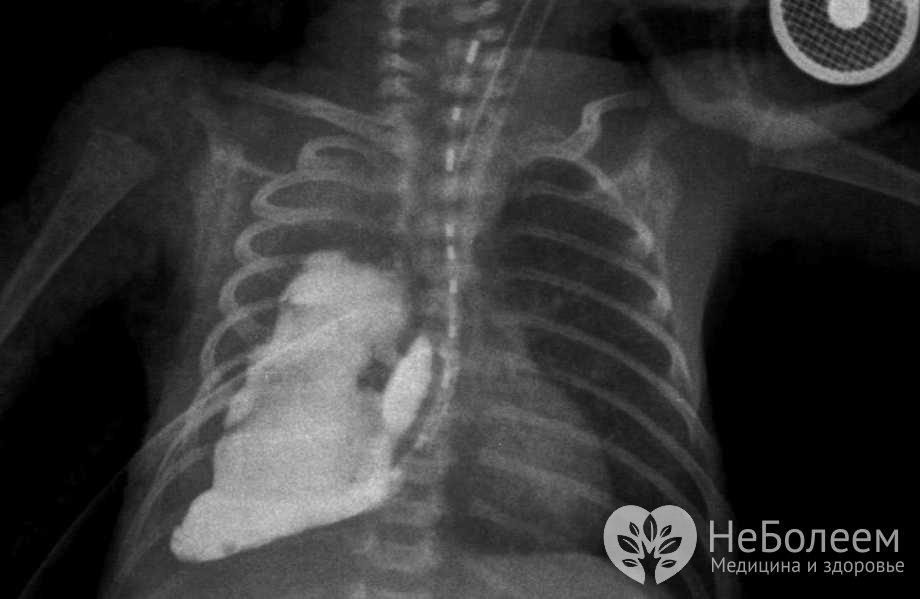

Бронхолегочная дисплазия на рентгеновском снимкеИзначально бронхолегочная дисплазия рассматривалась как результат токсического воздействия высоких концентраций кислорода на ткань легких новорожденного при искусственной вентиляции легких (ИВЛ). В настоящее время большинство специалистов считают данную патологию полиэтиологическим заболеванием, к развитию которого могут приводить:

Для подтверждения диагноза выполняют рентгенографию легких. На рентгенограмме могут выявляться: